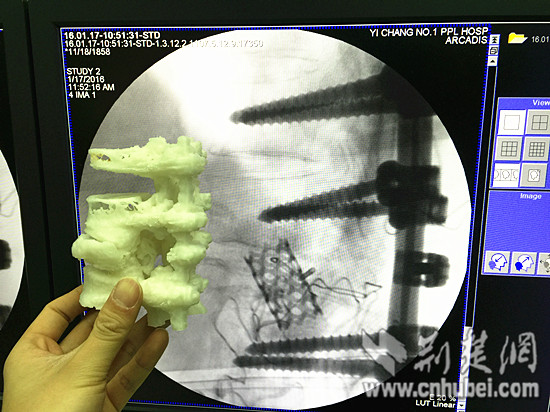

3D打印清楚的显示了脊柱内部情况

医生结合3D模型制定手术方案

为了解决手术中存在的这一问题,宜昌市第一人民院骨科决定采用3D打印技术,通过数据模拟打印出脊柱,在手术前可以看到CT图上看不到的内部情况。

宜昌市第一人民院骨科副主任医师覃涛,既是医院的骨科医生,也是该院3D数字骨科学研究团队的核心成员。“我们从2009年就在研究3D数字化手术,在行业内比较领先。”覃涛说,“将前期多角度的CT数据处理成3D数据后,我们通过3D打印技术迅速为该患者制作了1:1脊柱三维模型,立体、精确地显示脊柱骨折部位的内部情况。最终为患者精准、快速地实施手术。